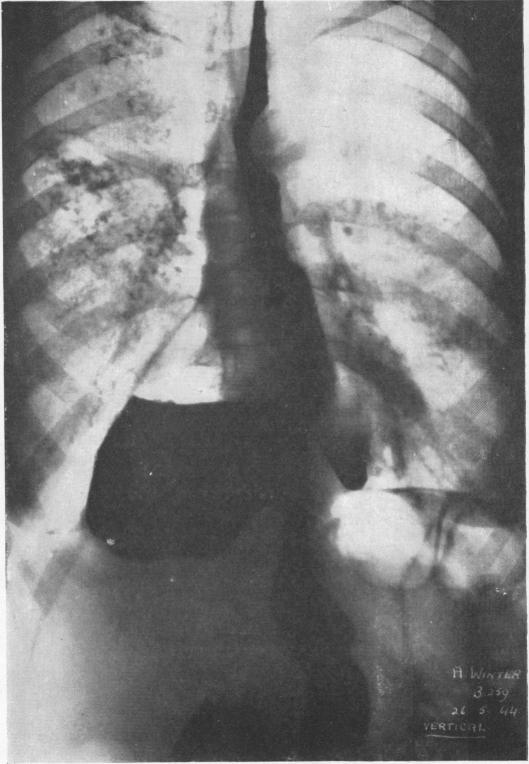

Fifty-seven cases of diaphragmatic hernia and eventration.

Thorax. 1950 Dec;5(4):343-61. doi: 10.1136/thx.5.4.343.